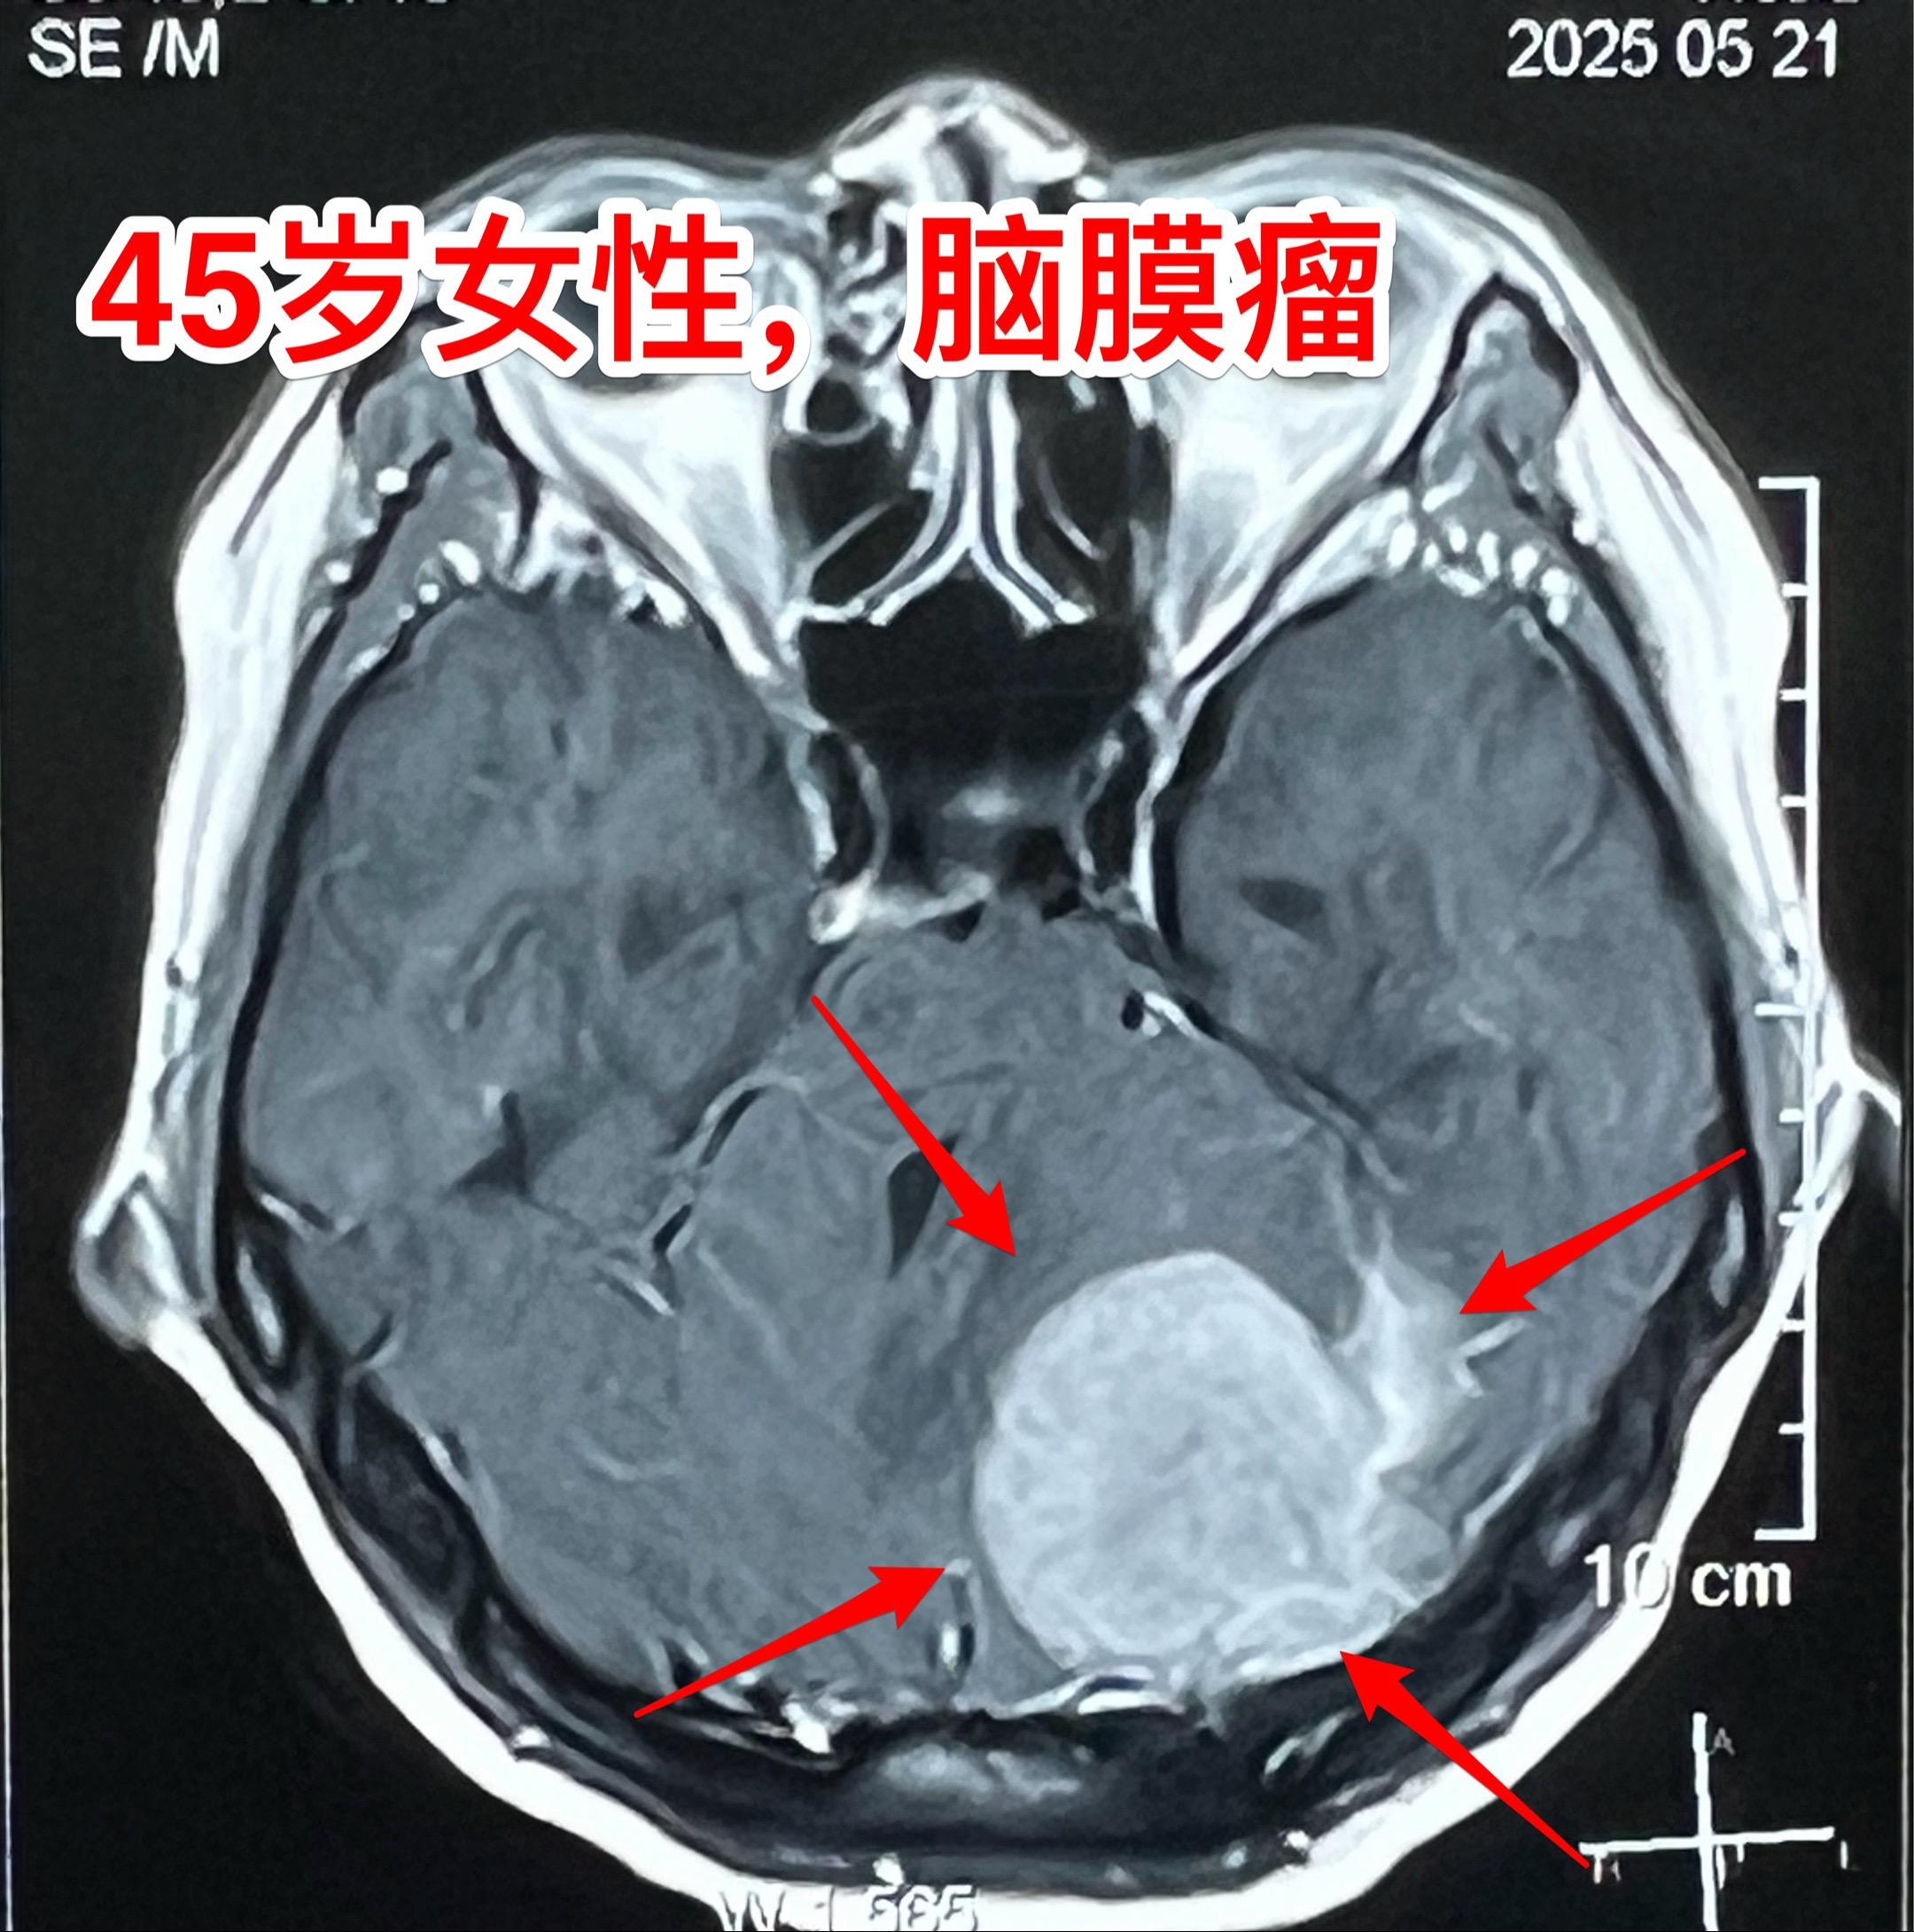

45岁女性因头痛发现脑膜瘤。45岁呼伦贝尔女性,在北京工作。头痛症状不剧烈,无呕吐。到医院就医,作头部CT检查发现可疑问题,再作磁共振检查发现左侧小脑表面有个巨大的脑膜瘤,伴有脑积水。 5月23日作了手术(只能是开颅手术)将脑膜瘤完全切除。 这样的脑膜瘤属于相对浅表位置的肿瘤,比颅咽管瘤手术要容易的多。脑膜瘤虽然是良性肿瘤,也有一定的复发率。